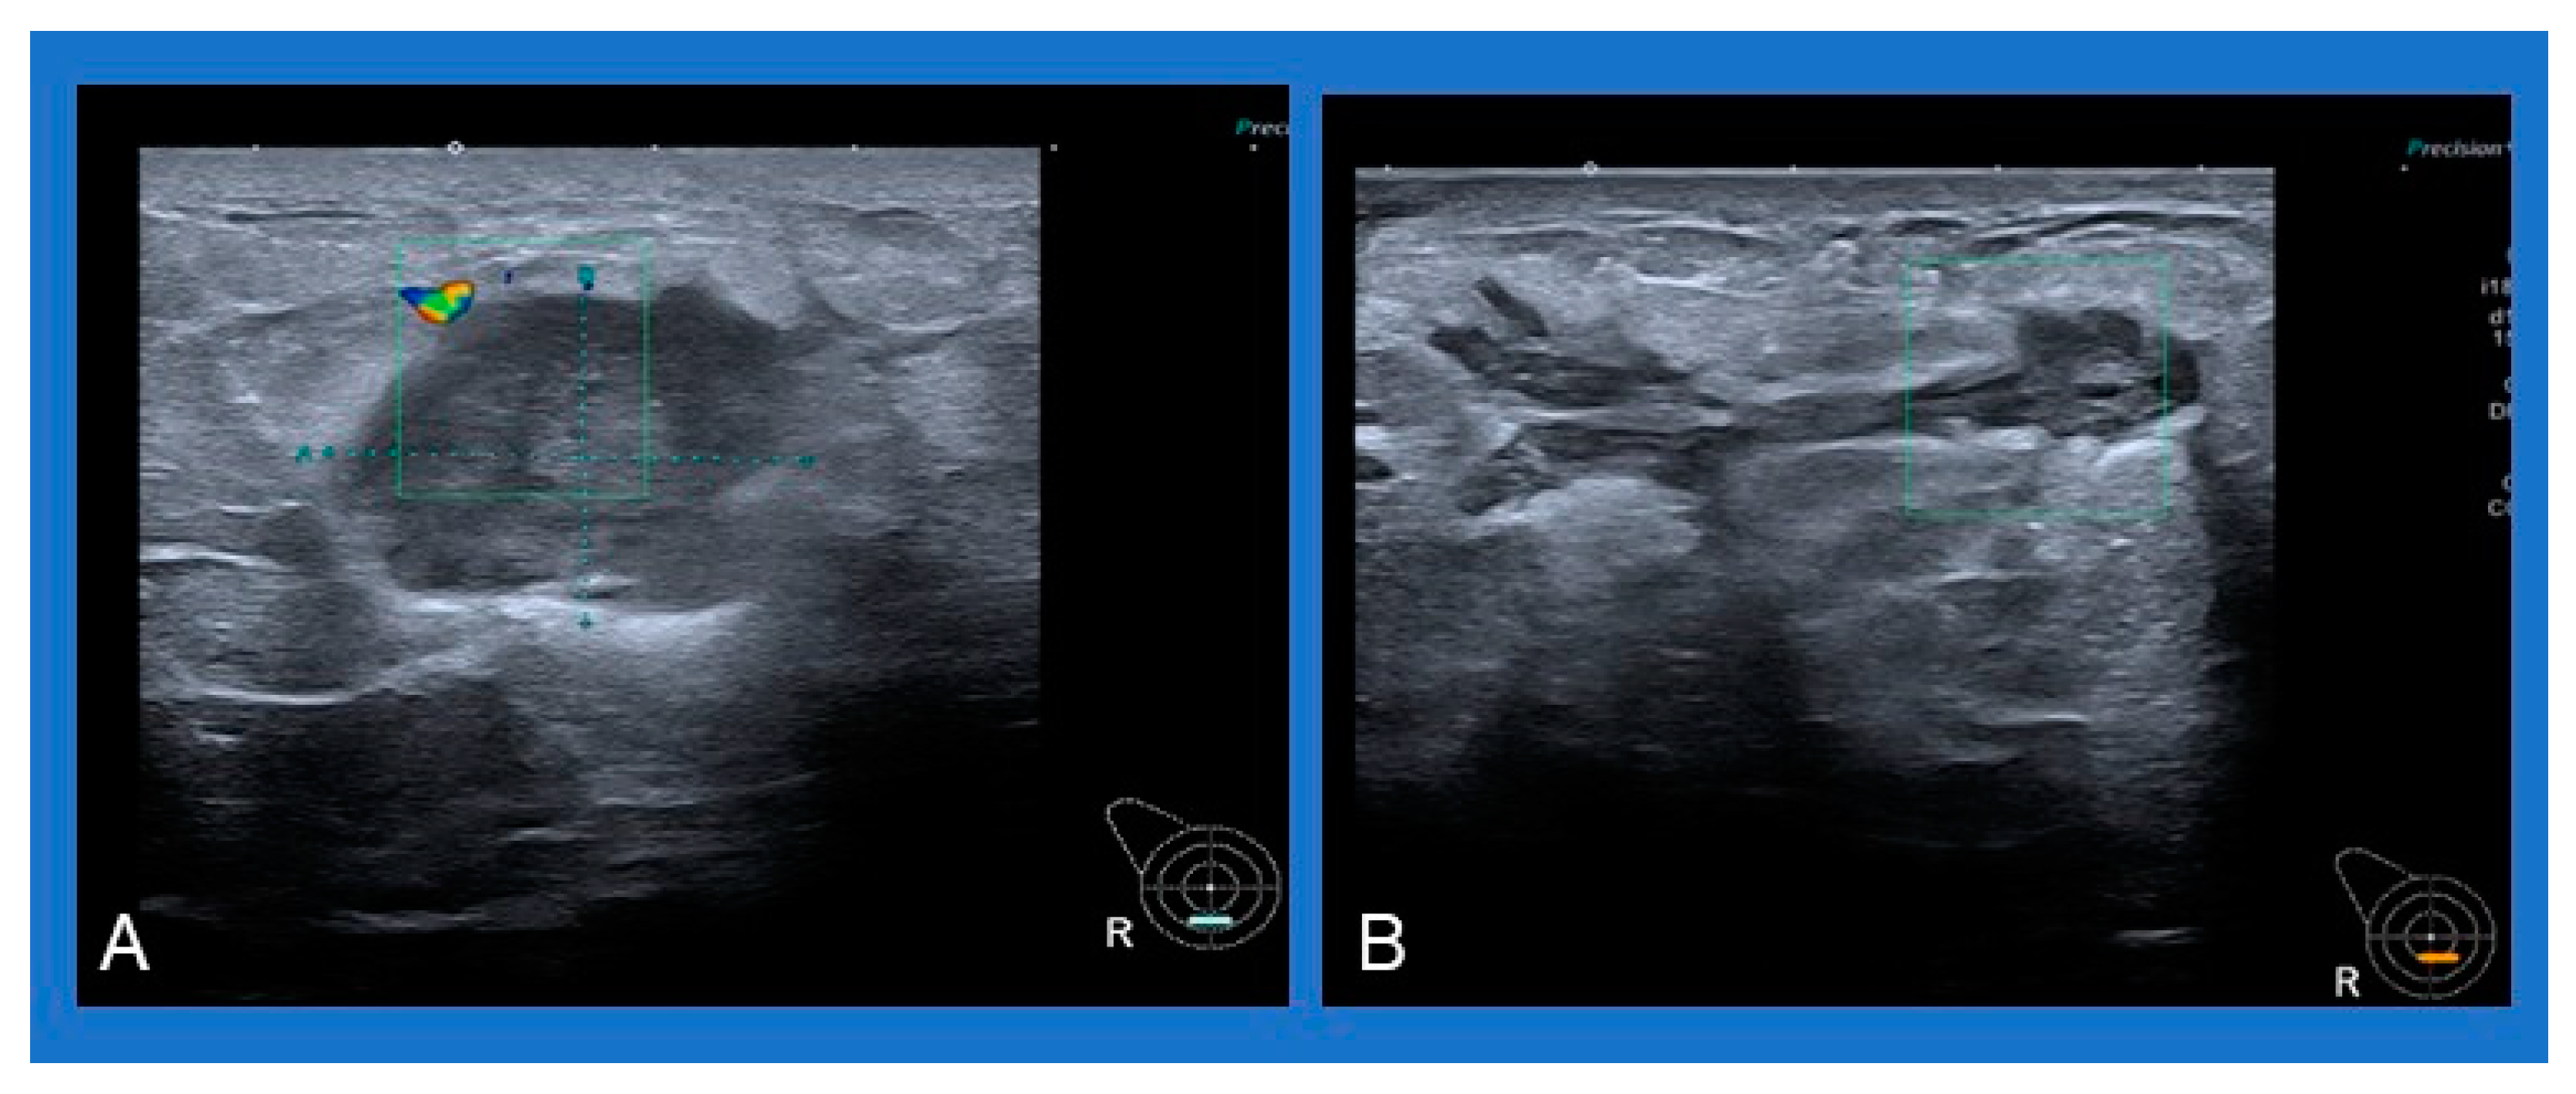

2.5. Presentation on Imaging

- Alikhassi, A.; Azizi, F.; Ensani, F. Imaging features of granulomatous mastitis in 36 patients with new sonographic signs. J. Ultrasound 2020, 23, 61–68. [Google Scholar] [CrossRef]

- Pluguez-Turull, C.W.; Nanyes, J.E.; Quintero, C.J.; Alizai, H.; Mais, D.D.; Kist, K.A.; Dornbluth, N.C. Idiopathic Granulomatous Mastitis: Manifestations at Multimodality Imaging and Pitfalls. Radiographics 2018, 38, 330–356. [Google Scholar] [CrossRef]

- Sripathi, S.; Ayachit, A.; Bala, A.; Kadavigere, R.; Kumar, S. Idiopathic granulomatous mastitis: A diagnostic dilemma for the breast radiologist. Insights Imaging 2016, 7, 523–529. [Google Scholar] [CrossRef]

- Yildiz, S.; Aralasmak, A.; Kadioglu, H.; Toprak, H.; Yetis, H.; Gucin, Z.; Kocakoc, E. Radiologic findings of idiopathic granulomatous mastitis. Med. Ultrason. 2015, 17, 39–44. [Google Scholar] [CrossRef] [PubMed]